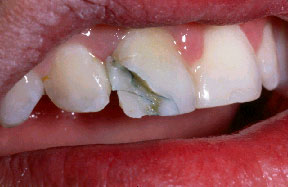

Si no se coloca el composite en las superficies vestibulares de las áreas interproximales creando un reborde de 180 grados para estabilizar los dientes, las fuerzas que afectarán a la férula durante la función masticatoria puede causar que el diente se separe de la férula. Este es un ejemplo de una férula donde el diente se ha separado debido a inadecuada aplicación del composite sobre la superficie vestibular.